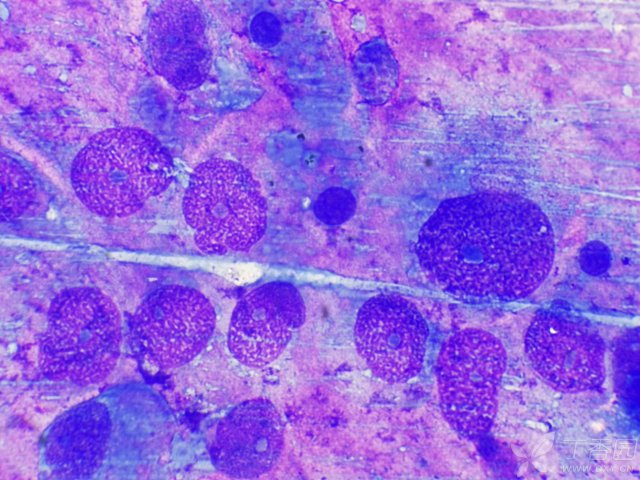

宠物肿瘤是什么、多可怕、能否治疗?一文揭秘!肿瘤是什么? 细胞生长失控之后,形成的团块就称之为肿瘤。肿瘤可以分为良性肿瘤和恶性肿瘤两种。 良性肿瘤是指不规则生长的细胞聚集成团块,与周围组织结合在一起,具有分界线没有侵犯周围组织。 恶性肿瘤是指突变基因失控,侵犯周围组织。 造成狗狗肿瘤的原因 引起肿瘤的原因很...

体内有恶性肿瘤的人,身体一般会有7个表现,平时多留意肿瘤可以分为良性及恶性两大类,通常情况下,良性肿瘤被称作“瘤”,而恶性肿瘤则被称作“癌”。 体内有恶性肿瘤的人 身体一般会有7个表现 体重无故下降: 恶性肿瘤细胞消耗体内的营养物质,导致患者在没有刻意节食或增加运动量的情况下体重明显下降。 持续性...